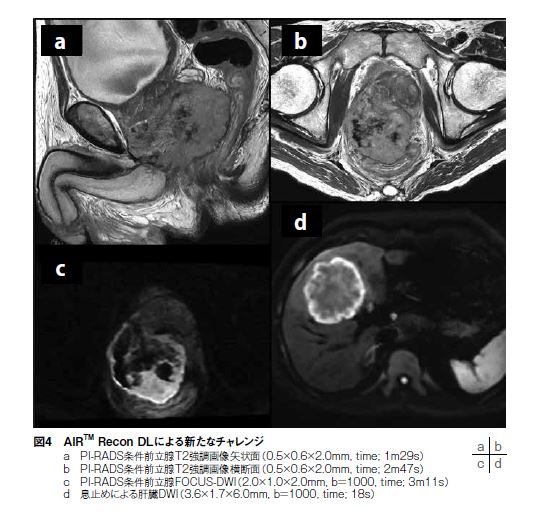

画質の大幅な向上により、従来再構成の時には撮像していなかった新しい撮像にチャレンジできるようになった。一例として、前立腺MRIでは撮像や読影の標準化を目指してPI-RADS1)という指針が作成されたが、面内分解能0.4×0.7mm以下、スライス厚3.0mm以下というように高分解能が要求されるため、SNRや撮像時間を考慮すると従来再構成法では臨床に採用することは困難であった。しかし、AIR™ Recon DL再構成により、撮像時間の延長無く、分解能とSNRを共に向上することができたため、PI-RADS撮像条件をクリアしながらも前立腺MRI検査の時間短縮も実現できた(図4a~c)。他にも、息止めが必要な部位の撮像には息止め時間の制限から、従来再構成では得られる画質にも限界があった。

AIR™ Recon DL再構成により、以前はSNRが乏しかった息止めDWIを上腹部検査において新たにルーチンとして組み込むことができた(図4d)。